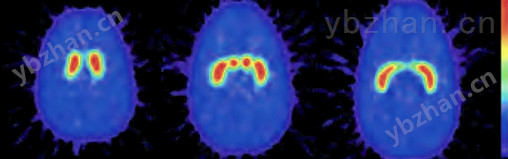

纹状体幻影使用PET或SPECT优化患者的定量成像。这个幻影是基于*个标准的RSD头部与颅骨切割,以插入或移除脑壳很容易。鼻腔和上颌窦内充满泡沫,质量密度为0.23 g/cc。

脑壳有五个隔间,可以分别被填满:左右尾状核,左右壳核,以及大脑的其余部分。这使得可以获得不同的尾状核与壳核比率以及不同的纹状体与背景比率;这也可以检查左右纹状体活动的差异。脑壳的体积约为1260毫升。尾状核和壳核的体积分别为5.4 ml和6.0 ml。

纹状体摄取的定量并不是简单的,因为它取决于许多因素,包括使用的放射性核素类型(Tc-99m、I-123或F-18)、成像因素(如准直器类型、散射和衰减量)和图像处理参数(如散射和衰减校正技术、重建滤波器的类型、切片厚度、感兴趣区域大小及其位置)。

在正常受试者中,壳核和尾状核的头部是*个小的结构,在轴向平面上的典型尺寸为7-15mm(与系统分辨率相当)。由于部分体积效应对于尺寸小于系统分辨率两倍的物体更为重要,成像和重建参数的选择在计算用于测量大脑纹状体相对摄取的纹状体-枕比时至关重要。